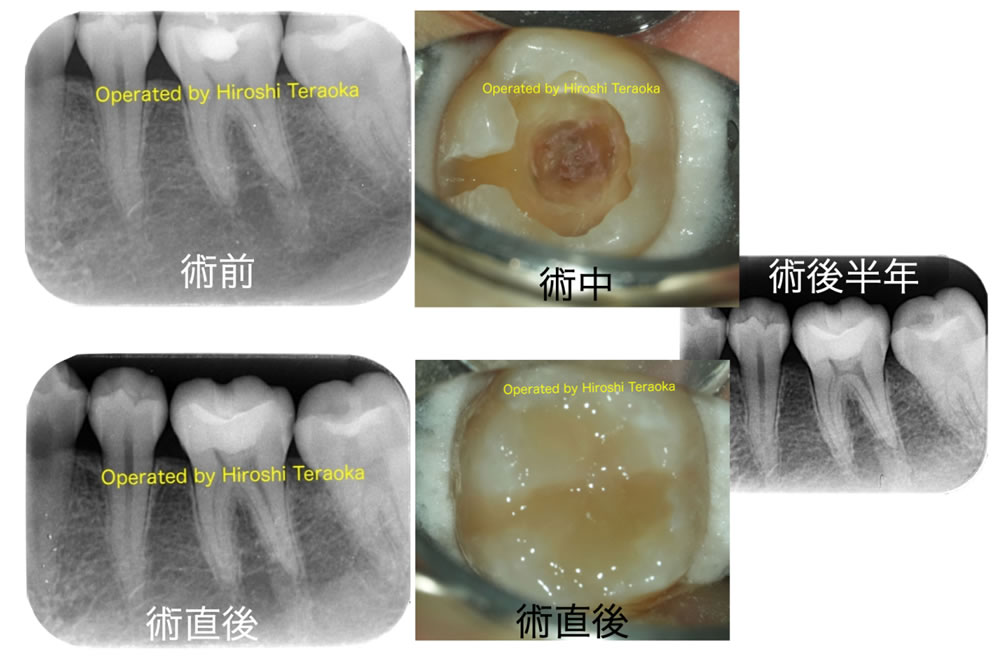

症例 1

20代女性。痛みはないが左下の虫歯を主治医に指摘されたので治療して欲しい(左下6)。

| 治療内容 | 歯の神経の部屋に近いカリエス処置が前医により行われていた。詰め物の下に黒い透過像が認められカリエスが疑われる。患者には自覚症状はなく歯髄検査(電気刺激、冷熱刺激)で正常反応。歯髄診断を正常歯髄、根尖部診断を正常な根尖周囲組織とした。 ラバーダム下でむし歯を全て除去、中心の茶色い部分はカリエスではないと判定された。 術直後のX線写真では隙間はなく過不足なく充填されている事が確認できる。 |